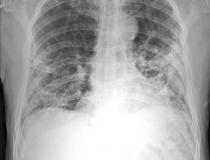

ITN has created a photo gallery designed to show the global impact of the novel coronavirus (COVID-19, SARS-CoV-2) in healthcare, and the world. The images are from ITN staff members, submitted from readers on Facebook, and shared from press releases, hospitals and government public relations sources. This page will be updated regularly with new photos.

We'd love to share your stories of survival as well. You are welcome to submit your images, along with captions and photo credits, to [email protected].